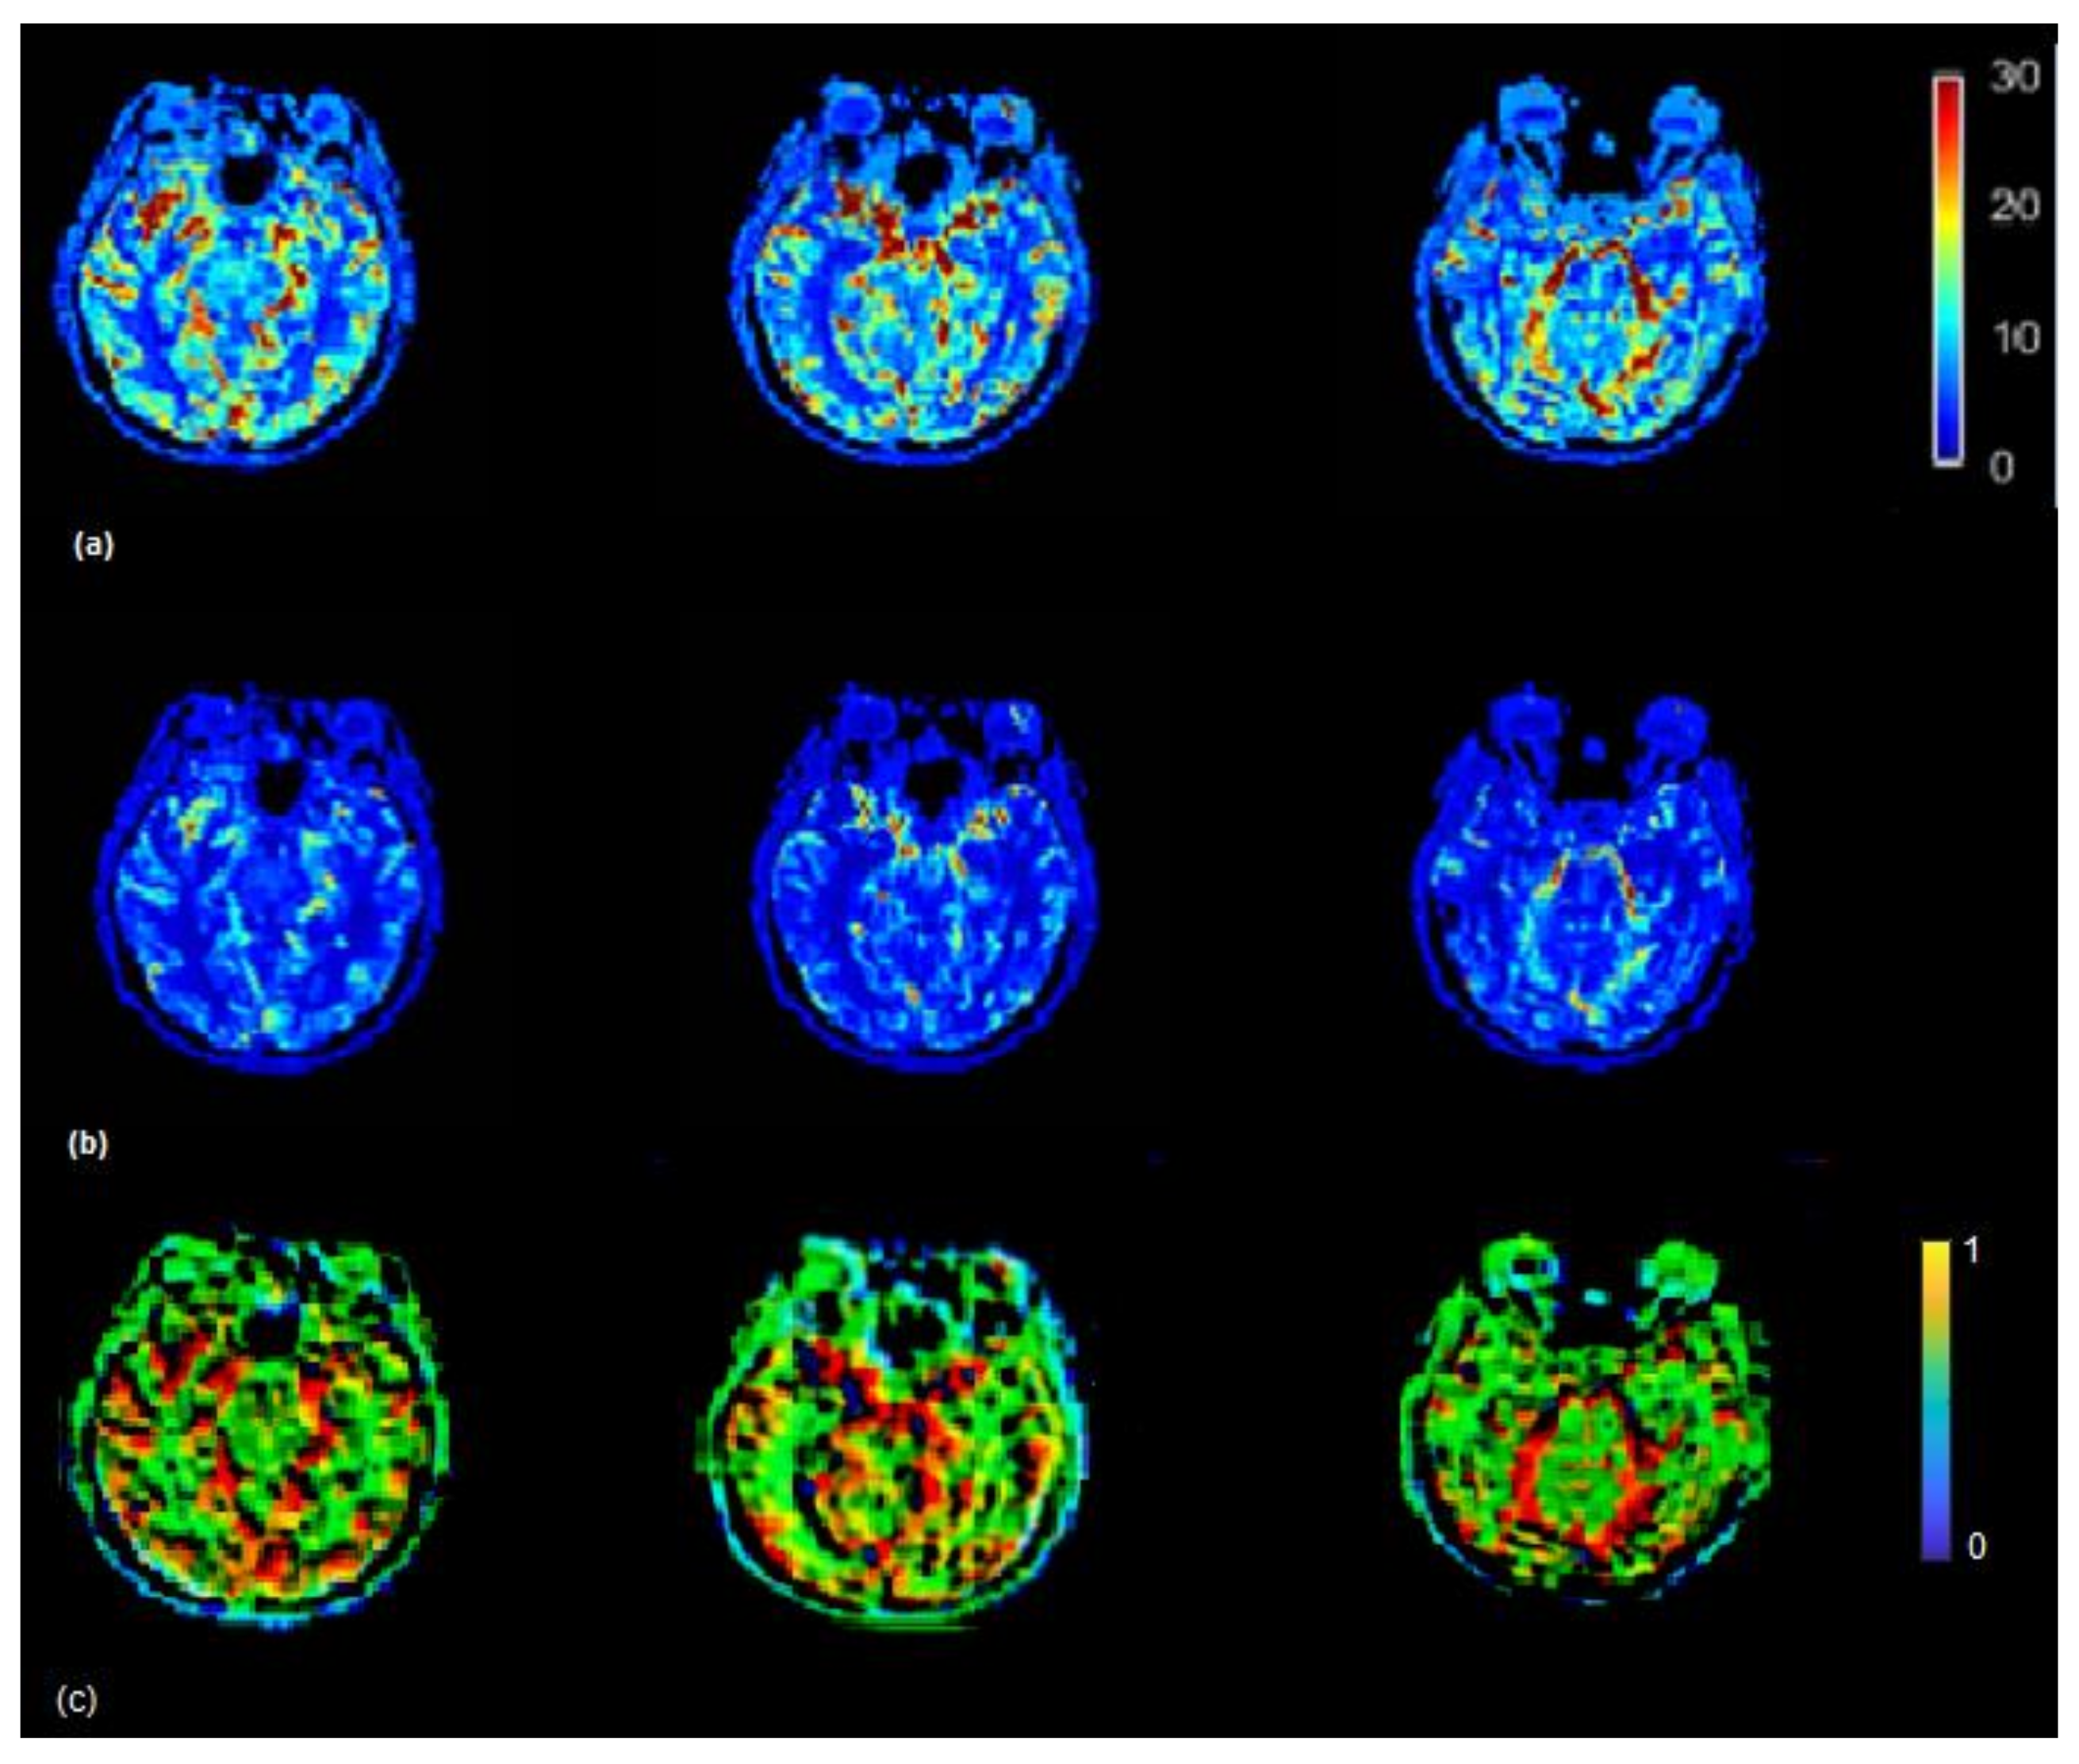

The CBF brain map was generated in the absence of scaling of AIF as well as by using the VOF rescaling approaches (Figure 5). In some cases, relative to the CBF map generated by using non-rescaled AIF, the CBF map generated by rescaled AIF approaches showed increased CBF values on the slices in the left and right hemispheres (red color) (visible in Figure 5). From Equations (5) and (6), it follows that the ratio of scaled and unscaled CBF values should be the scaling factor k. The images of the ratio of scaled and unscaled maps are expected to show the factor k for every voxel (Figure 5c). The mean CBF values, based on all 15 subjects using non-rescaled (AIF ROI width = 5 voxels) and VOF approach, were 43.98 and 61.16 mL/100g/min, respectively. The mean CBF values for AIF-rescaled and peak scaled approach were 57.10 and 47.10 mL/100g/min, respectively. At individual level, all the fifteen patients in this study did not follow similar pattern of underestimated CBF values due to the PVE. This has been demonstrated by studying the association of increasing degree of the PVE with deviation of CBF (Supplementary Material, Figure S1). To generalize, we need a larger dataset to conclude whether the scaling corrects the underestimation of CBF, as this could vary patient to patient in a small cohort.

Figure 5.

(a) CBF (mL/100 g/min) map generated by using rescaled AIF (b) and non-rescaled AIF (bottom). CBF map generated using rescaled AIF represents increased CBF values in the shown axial brain slices. CBF maps from non-rescaled AIF display mostly all the ROIs with decreased blood flow which makes it difficult to locate the regions which actually have a decreased flow. CBF images derived using rescaled AIF display ROIs with increased flow (red color) which helps to segregate the regions with decreased blood flow. This may help clinicals to identify the infract regions as well as regions with decreased blood flow on visual brain CBF images. (c) Maps illustrating the ratio between CBF values derived from the scaled and the non-scaled AIF.

The Tmax (seconds) map was generated using the rescaled AIF (VOF approach) (Figure 6) (top) and non-rescaled AIF (Figure 6) (bottom). The Tmax map generated using the rescaled AIF showed increased values in the axial brain slices in the left and right hemispheres. The mean Tmax values (range of 0–12 s) based on 15 subjects using non-rescaled (AIF ROI width = 5 voxels) and VOF approach were 4 s and 7 s, respectively. The derivation of Tmax is performed from the residue function (R(t)), which is achieved by deconvolution of Equation (6). Tmax is the argument, i.e., ‘t’ of the maximum of R(t). The deconvolution utilizes a matrix method called the circulant singular deconvolution, which is sensitive to the peak amplitudes of AIF (cSVD) [23]. The changed AIF amplitude used in the cSVD algorithm shifts the maximum of R(t) to a higher time points ‘t’ which accounts for higher Tmax values. The change in Tmax is consistent with a previous study where different AIFs with changed amplitudes and similar shape selected by different algorithms resulted in change of Tmax values [1]. The increased Tmax maps generated by the rescaled AIF may allow clinicals to visualize the critically hypoperfused regions which are likely to be salvageable.

Figure 6.

Tmax (seconds) map generated by using rescaled AIF (a) and non-rescaled AIF (b) for one subject. Tmax map generated using rescaled AIF represents increased values in the shown axial brain slices.